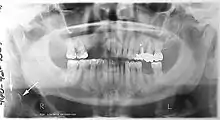

صورة الأشعة البانورامية أو التَّصْويرُ الشُّعاعِيُّ البانُورامِيّ (بالإنجليزية: panoramic radiograph) هي أشعة سينية بانورامية لفحص الأسنان للفكين العلوي والسفلي. تكون الصورة ثنائية الأبعاد لنصف دائرة من الأذن إلى الأذن. التصوير الشعاعي البانورامي هو شكل من أشكال التصوير المقطعي للمستوى البؤري. وهكذا يتم التقاط صور من عدة مستويات لعمل الصورة البانورامية المركبة، حيث يكون الفك العلوي والفك السفلي في النطاق البؤري والأجسام السطحية والأعمق من النطاق غير واضحة.

يتم استخدام صورة أشعة البانوراما من قبل المتخصصين في الرعاية الصحية لتوفير معلومات عن:

- تشخيص ضرس العقل المنطمر والتخطيط للعلاج. الاستخدام الأكثر شيوعًا هو تحديد حالة أسنان الحكمة وإصابات الفكين.

- فقدان العظام حول السني وإصابة العظم حول ذروة جذر السن.

- العثور على مصدر ألم الأسنان، ولتشخيص الأسنان جميعها في الفم.

- التقييم لوضع زرعات الأسنان.

- التقييم لتقويم الأسنان. قبل وبعد عمله.

- تشخيص تشوهات النمو مثل ورم زوايا الفك (cherubism)، خلل التعظم الترقوي القحفي (cleido cranial dysplasia)

- السرطانة (Carcinoma) وعلاقتها بالفكين

- خلل المفصل الصدغي الفكي والتحام المفصل.

- تشخيص الساركوما العظمية، الورم الأرومي المينائي، سوء التغذية العظمي الكلوي الذي يؤثر على الفكين و نقص فوسفات الدم.

- التشخيص وتقييم ما قبل الجراحة وما بعد الجراحة للرضوض الفموية والفكية، على سبيل المثال الكسور السنخية السنية وكسور الفك السفلي.

- الحصوات اللعابية (Sialolithiasis).